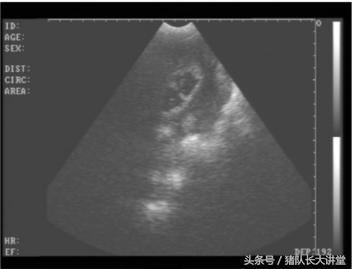

23天的B超图

2、这里只说下B超因为本人用的也比较多;

A、可以较为准确的测出是不是有小猪,具体使用办法,根据说明使用,大家也可以提出问题;关注,一般你检测有的就是有了,单是检测没有的时候应该多视察;